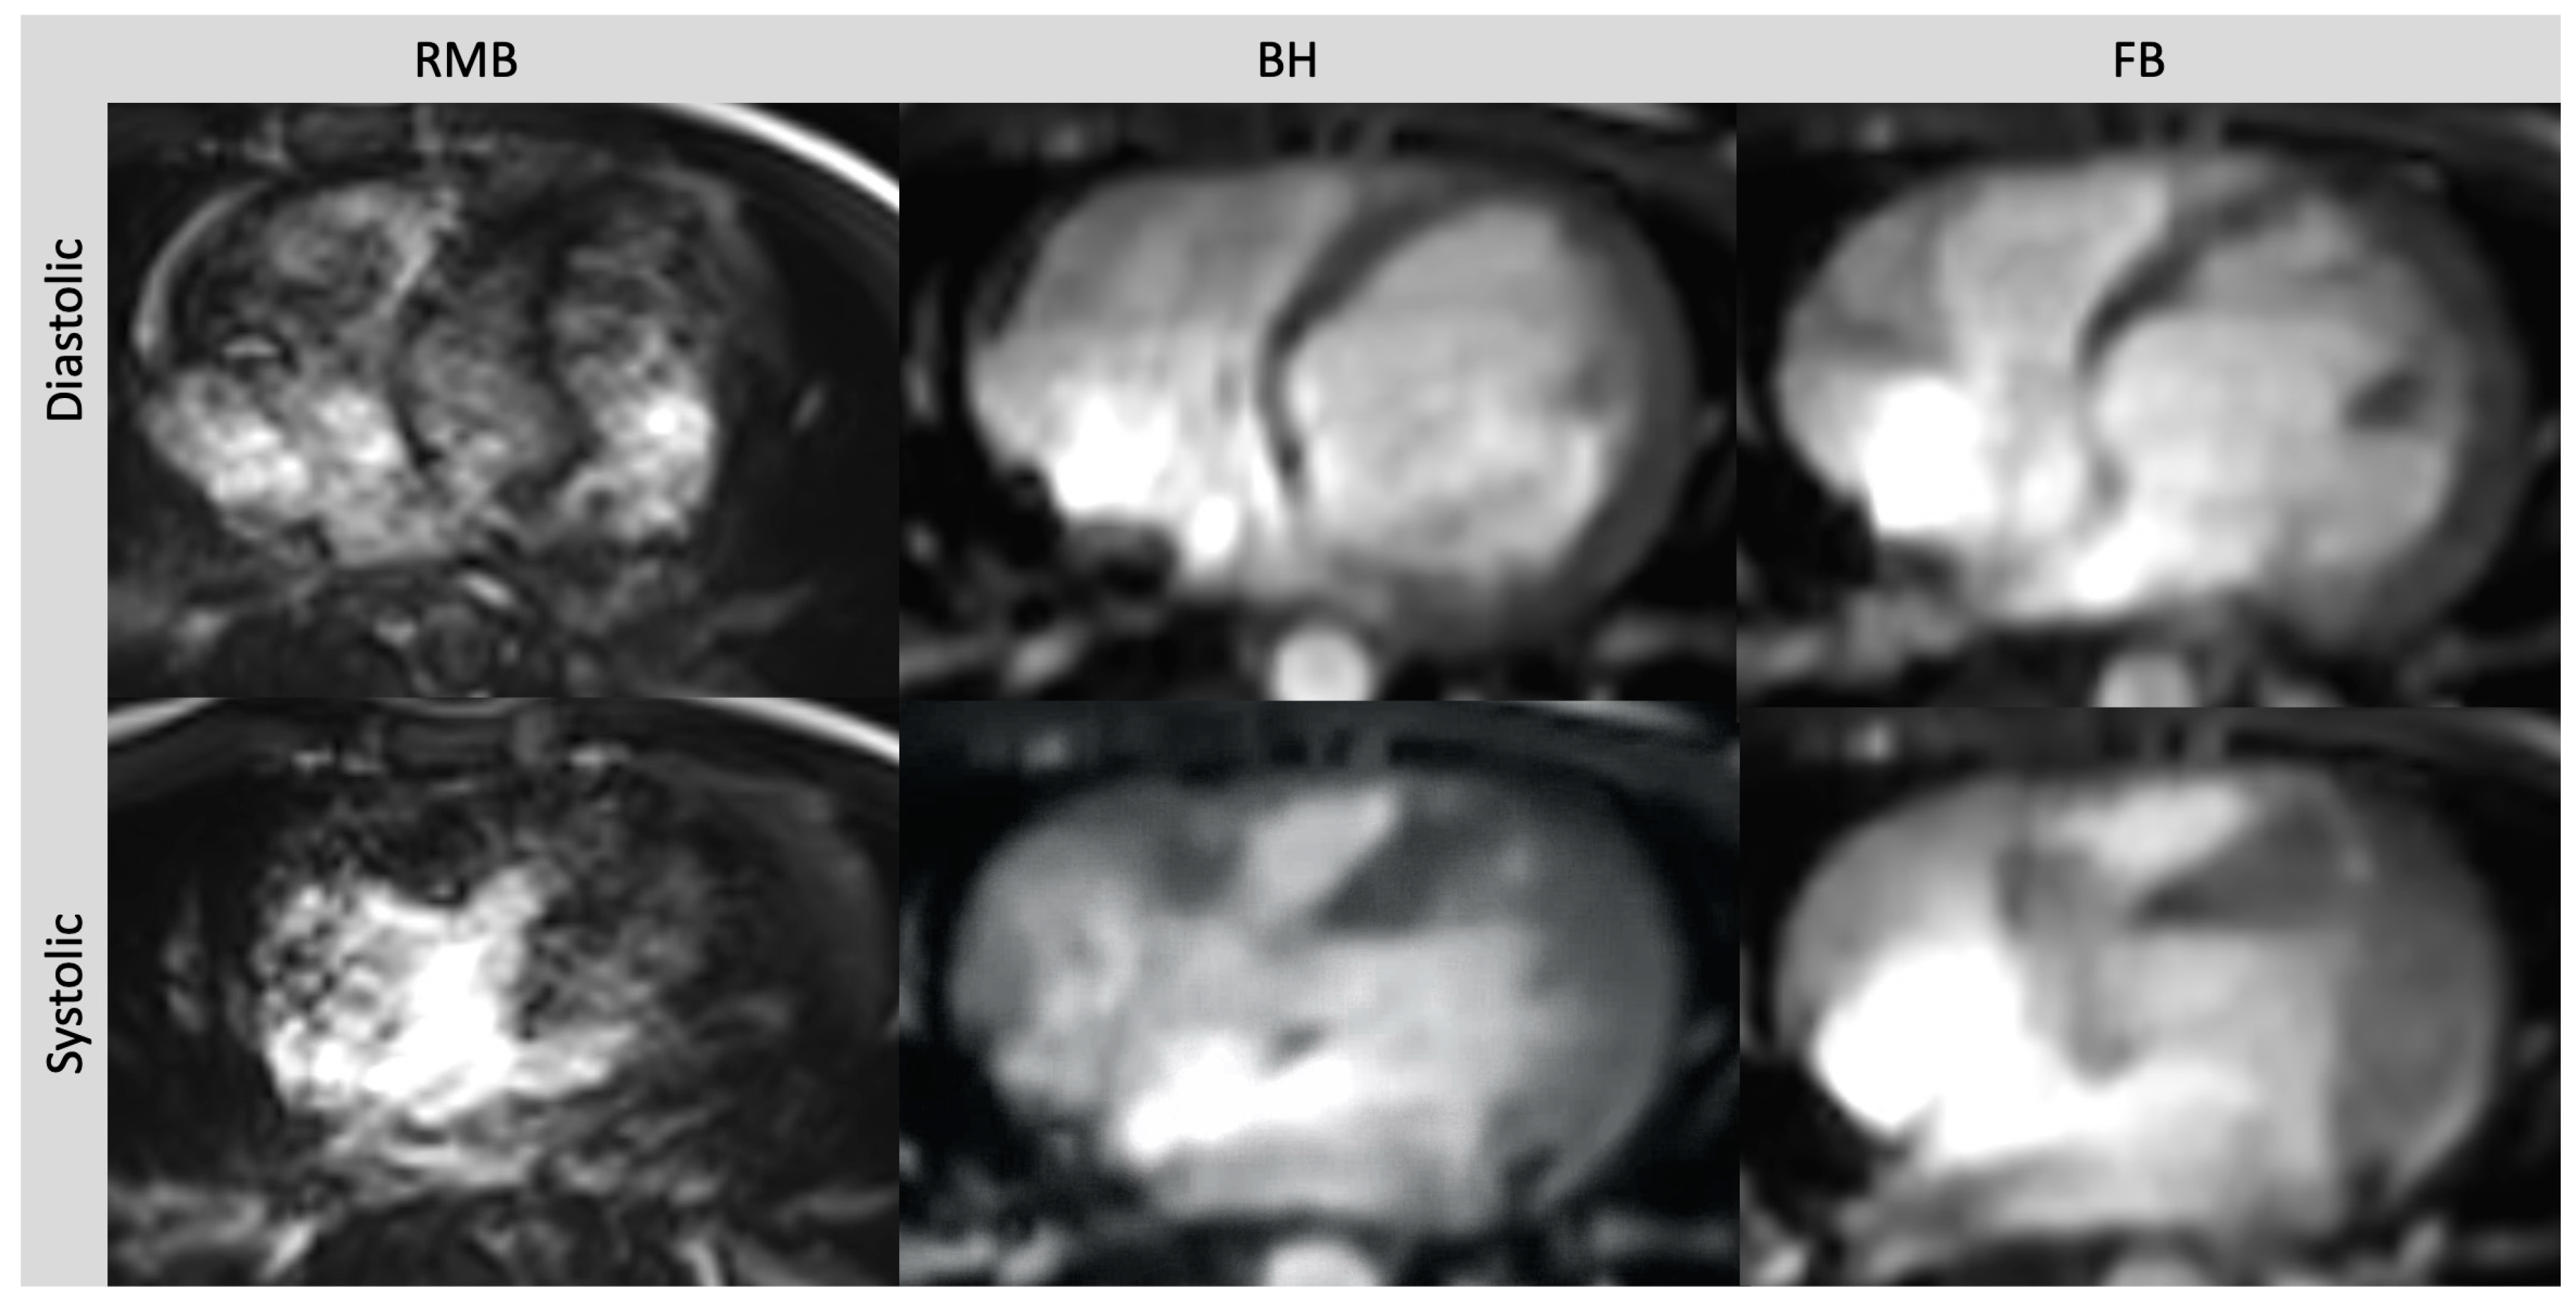

Figure 2.

Axial slices of all three cine sequences in systolic and diastolic phases in a patient with severe arrhythmia. Severe artifacts in RMB rendering volumetric evaluation insufficient. Image quality in FB and BH images is reduced but still diagnostic. Retrospective segmented multi-breath hold (RMB), real-time single/double breath hold (BH), real-time free breathing (FB).

Comparing all three methods, the best image quality was provided by RMB (4.5; range 2 to 5) compared to BH (3.9; range 3 to 5; p = 0.04) and FB (3.6; range 3 to 5; p < 0.01). The image quality with BH was slightly better than with FB but the difference did not reach statistical significance (p = 0.07). The diagnostic confidence was comparable between RMB and BH (p = 0.65) and between RMB and FB (p = 0.84). With RMB, 90% of the cases were rated with high, 5% with intermediate, and 5% with low confidence, whereas with CS-BH and CS-FB, 80% and 75% were rated with high confidence, respectively, and 20% and 25% with intermediate confidence, respectively. Poor image quality with RMB was due to artifacts caused by arrhythmia, whereas BH and FB delivered diagnostic-level image quality in this case (Table 2). Representative images from RMB, BH, and FB are shown In Figure 1 and Figure 2.

RMB relies on the regular periodicity of the heart rate to acquire data across multiple cardiac cycles, which are then merged to reconstruct a complete cine slice representing successive heartbeats. However, in the presence of arrhythmia, artifacts can occur due to the reconstruction using data from different phases of the cardiac cycle [27,28]. To mitigate this, arrhythmia rejection algorithms can be applied but may result in exceedingly long breath holds [29]. By incorporating parallel imaging, CS can achieve acceleration rates that enable real-time cardiac cine imaging. This helps to avoid misreferencing of the image data throughout the cardiac cycle [30]. Within our patient collective, we encountered a single patient who experienced non-diagnostic image quality in RMB due to artifacts related to arrhythmia. In this particular patient, ventricular volumetry was not feasible in RMB, whereas both CS sequences consistently provided diagnostic image quality, overcoming the challenges posed by arrhythmia-related artifacts (Figure 2). This is in line with several other studies that have demonstrated the superiority of real-time cine CS MRI images over retrospective gated acquisitions in patients with arrhythmia. In a study conducted by Longère et al. involving a cohort of 71 patients with arrhythmia, the implementation of compressed sensing real-time cine drastically reduced artifacts associated with arrhythmia. As a result, there was a marked improvement in the quality of cine images [29]. In a different study, carried out by Laubrock et al., real-time cine CS imaging was found to enhance the quality of images in 29 patients with atrial fibrillation. Volumetric analysis was feasible, albeit with slightly lower values compared to RMB, and ejection fractions remained comparable [31].